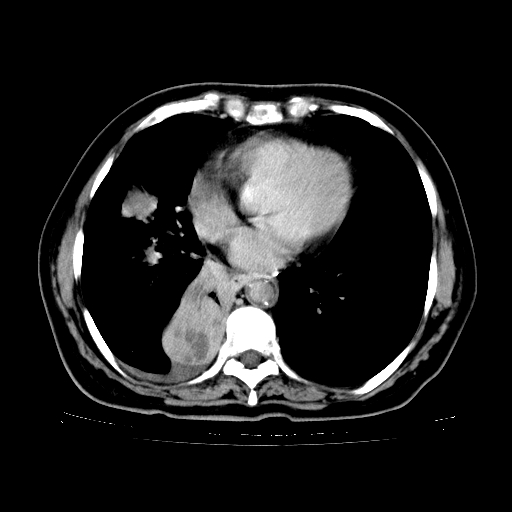

女,70岁,咳嗽、咳痰一个月,低热一周。

1、右肺占位,考虑周围型ca 。

2、右下肺软组织密度肿块影,考虑肺隔离征。

3、两肺肺结核(右肺下叶背段及左肺)。

4、主动脉夹层。

5、右侧少量胸腔积液。

支持,首先一元论解释。胸主动脉部分层面环形低密度,中心强化。环形影不强化。不象真假腔的改变。我考虑动脉炎,不太支持夹层动脉瘤-和大家的观点不一致,希望楼主让患者再做个心血管的彩超吧。